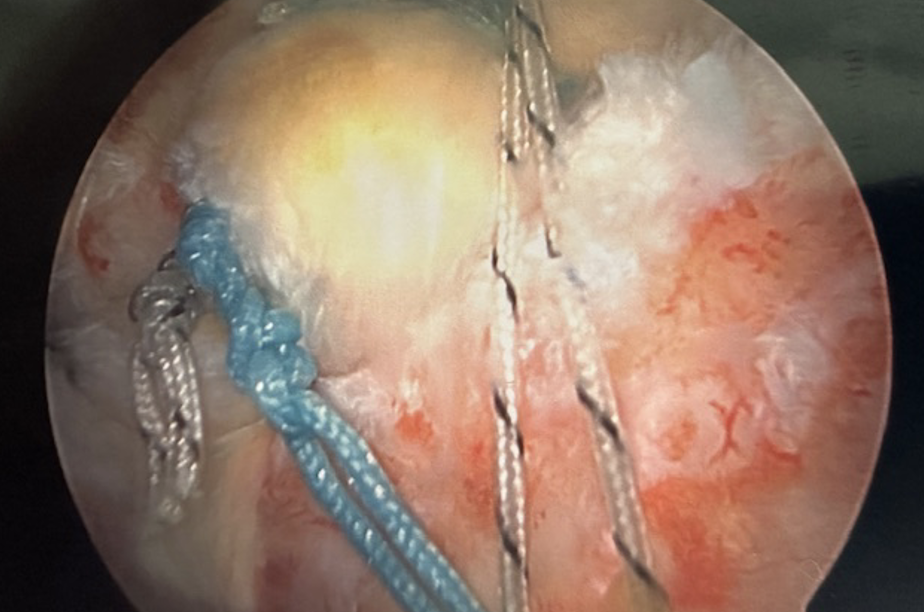

Arthroscopic picture of an Acute Rotator Cuff Repair - Before & After